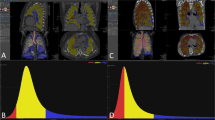

All HRCT images were analyzed by a single trained radiologist using a free DICOM viewer software (Osirix Version 8.0; Pixmeo SARL). For each slice, a semiautomatic segmentation of the lung parenchyma was performed in order to obtain an analysis of whole CT images. Afterward, the descriptive parameters of the quantitative analysis were calculated in different CT attenuation values, as previously described in detail [8,9,10,11,12,13, 15, 16, 18]. All histogram-based quantitative assessments were made in six different sessions by the trained radiologist (Table 1; Fig. 2). Due to the nature of quantitative measurement, agreement between observers has not been investigated. If necessary, minimal user intervention was performed to exclude pulmonary vessels, esophagus, trachea, and main bronchi.

An example of a quantitative high-resolution computed tomography evaluation. a All voxels between − 500 and − 700 HU for Method-1 (volume 191.6 cm3). b All voxels between − 500 and − 800 HU for Method-2 (volume 646.7 cm3). c All voxels between − 260 and − 600 HU for Method-3 (volume 314.9 cm3). d All voxels between − 400 and − 800 HU for Method-4 (volume 779.1 cm3). e All voxels between − 200 and − 1024 HU for Method-5 (volume 1852.7 cm3, mean lung attenuation − 719.4 HU, standard deviation 204.7, skewness 0.863, kurtosis − 0.144). f All voxels between − 400 and − 950 HU for Method-6 (volume 1497.7 cm3, mean lung attenuation − 753.2 HU, standard deviation 135.8, skewness 0.795, kurtosis − 0.215)